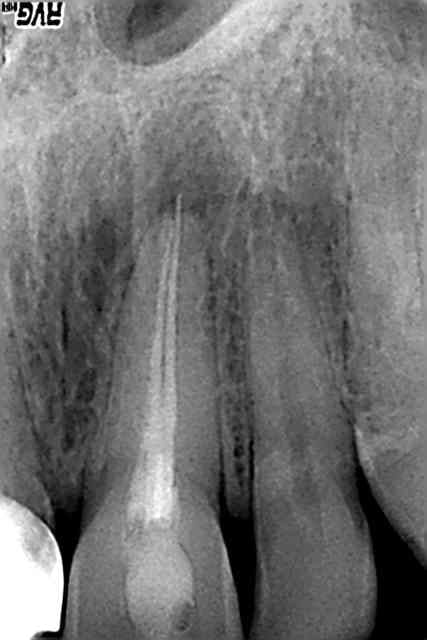

endo de ce matin... j'étais pas peu fier de moi! pas de radio avec tous les cones en place car le canal n'était pas assez large, meme pas assez large pour faire radio de 2 limes 10 en place! ca fait plaisir :)

les 2 premières radios sont les pré op, puis 1 radio lime en place (je pensais avoir les 2 limes dans les 2 racines vestibulaires, mais en fait cette radio m'a permis de me rendre compte que je n'avais pas désobturé la distale), puis les 2 cones en place (on ne pouvait pas mettre les 2 cones en meme temps à cause de la constriction), puis obturation de la mésiale: j'ai coupé le cone pour qu'il ne sorte pas de la bifurcation, et j'ai poussé le bout, enduit de ciment, avec une sonde/le reste du cone de gutta, puis pris une radio pour voir dans quel canal le morceau était allé; mis les cones de gutta en conséquence, pris une radio, puis thermocompacté... puis radio post op...